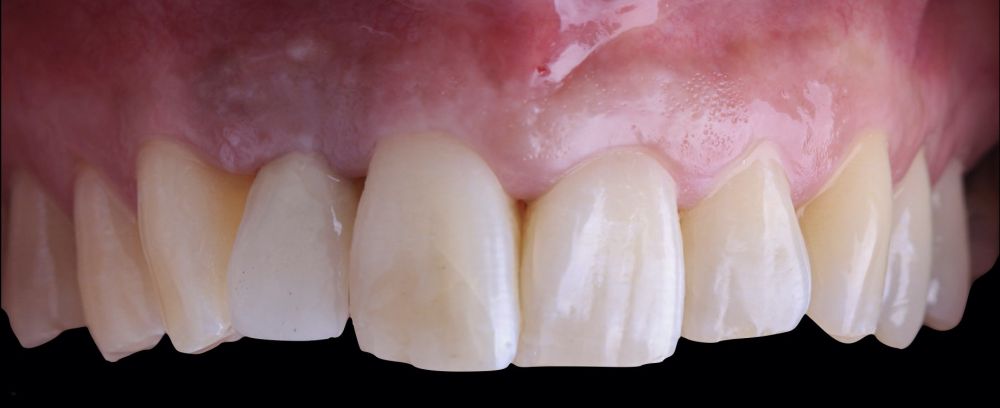

-Fase III: tres meses tras la colocación del implante, la situación del tejido blando era favorable (Figuras 5 y 6). Se tomó una impresión digital mediante escáner intraoral para la realización de un provisional atornillado de polimetilmetacrilato (PMMA). Respecto a la corona implantaria definitiva se realizó una restauración cemento-atornillada con una interfase de titanio nitrurado adaptando el diseño al perfil de emergencia ya consolidado con la prótesis provisional. La corona se realizó por CAD-CAM en zirconio con reducción completa y estratificación de cerámica feldespática de recubrimiento para zirconio (Figura 7).

El resultado clínico final fue satisfactorio cumpliendo las demandas estéticas del paciente. Los tejidos blandos estaban morfológicamente y dimensionalmente estables sin ningún signo de inflamación. Sin embargo, los cambios del tejido blando periimplantario (espesor volumétrico vestibular) fueron demostrados de manera cualitativa y cuantitativa (Figuras 8 y 9). En el postoperatorio inmediato (T1), la ganancia media obtenida al comparar T0 frente a T1 fue de 0,88 ± 0,15 mm con un incremento máximo de 1,1 mm. Al comparar T0–T2, se observó una ganancia media de 0,73 ± 0,23 mm. Es decir, se ha producido una contracción de volumen de 0,16 mm desde la colocación del injerto (T1) hasta pasado un mes y medio (T2).